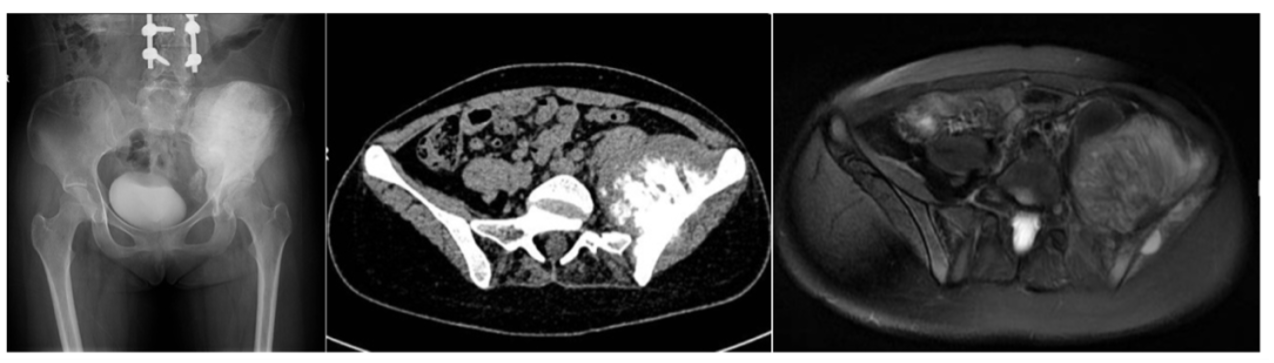

图:骨盆X线、CT和MR:左侧骨盆巨大肿瘤占位(I+II+IV区),左侧髂骨翼为中心的骨质破坏,周围巨大软组织肿块影,最大层面径线约为117*76*72mm。